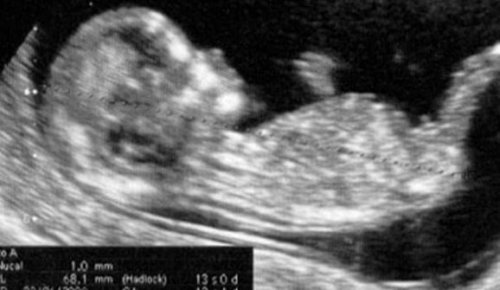

Raskauden toinen kolmannes ja uusi vaihe kohdussa kehittyvälle sikiölle on alkanut. 13. raskausviikko tarkoittaa sikiön olevan 6,5-10 senttimetriä pitkä ja painavan 13-20 grammaa. Sen kasvot alkavat muodostaa ainutlaatuisia piirteitään ja silmät ja korvat siirtyä lopullisille paikoilleen. Vauvalla on jo myös sormenjäljet.

13. raskausviikko on aikaa, jolloin voit vielä suorittaa ensimmäisen kolmanneksen ultraäänikuvaukset, jos niitä ei ole vielä tehty. Tämä on viimeinen askel niiden tarkastusten sarjassa, joita äidin on pitänyt käydä läpi aina raskauden toteamisesta lähtien. Ja tämä on se piste, jolloin ensimmäisen kolmanneksen arviointi saadaan päätökseen.